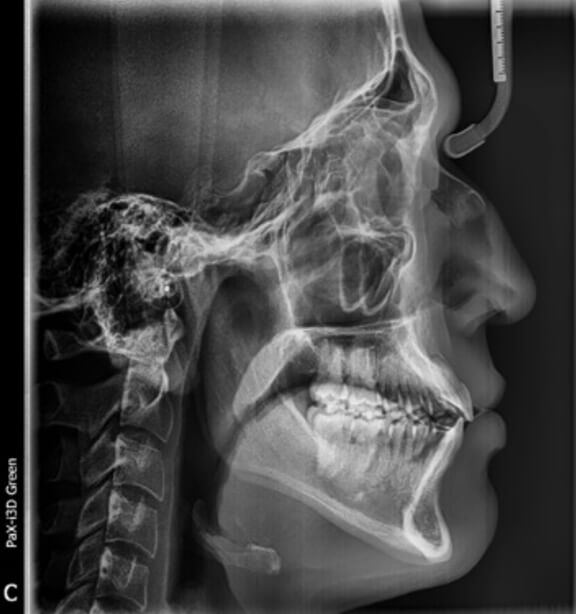

Estudios extraorales y radiográficos de inicio, al análisis clínico es diagnosticado como clase III, hiperdivergente, figura 1 perfil recto sin ninguna asimetría visible, figura 2.

Fig. 1 lateral de cráneo

El tiempo del tratamiento fue de un año cuatro meses, en su radiografía lateral de cráneo se ven la inclinaciones dentales figura 8 y a sus fotografías extraorales frente, perfil figura 9.

Fig.  8 lateral de cráneo